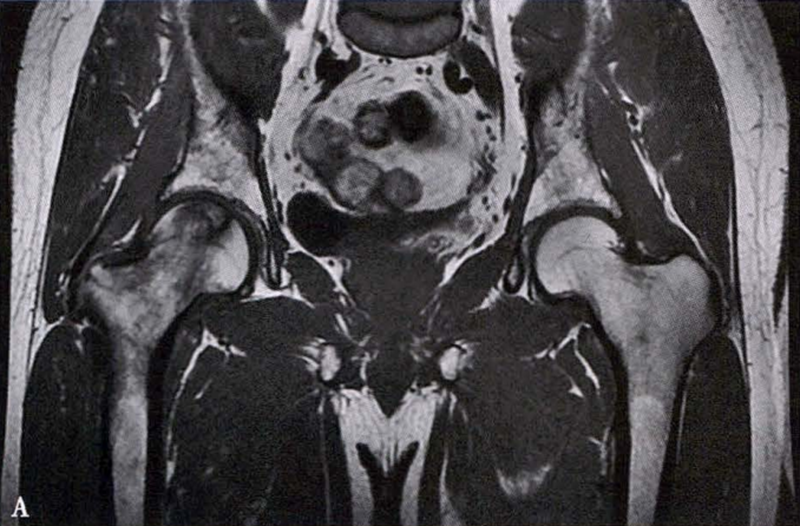

B.男性,31岁,双侧股骨头坏死,双侧均为Ⅲ期。X线片示双侧股骨头密度不均、股骨头稍变扁(B1)。MRI(T1加权像)示股骨头内多发不规则信号带(B2),股骨头内凸向大转子的双线征(白色箭)和软骨下骨骨折(白色三角)。